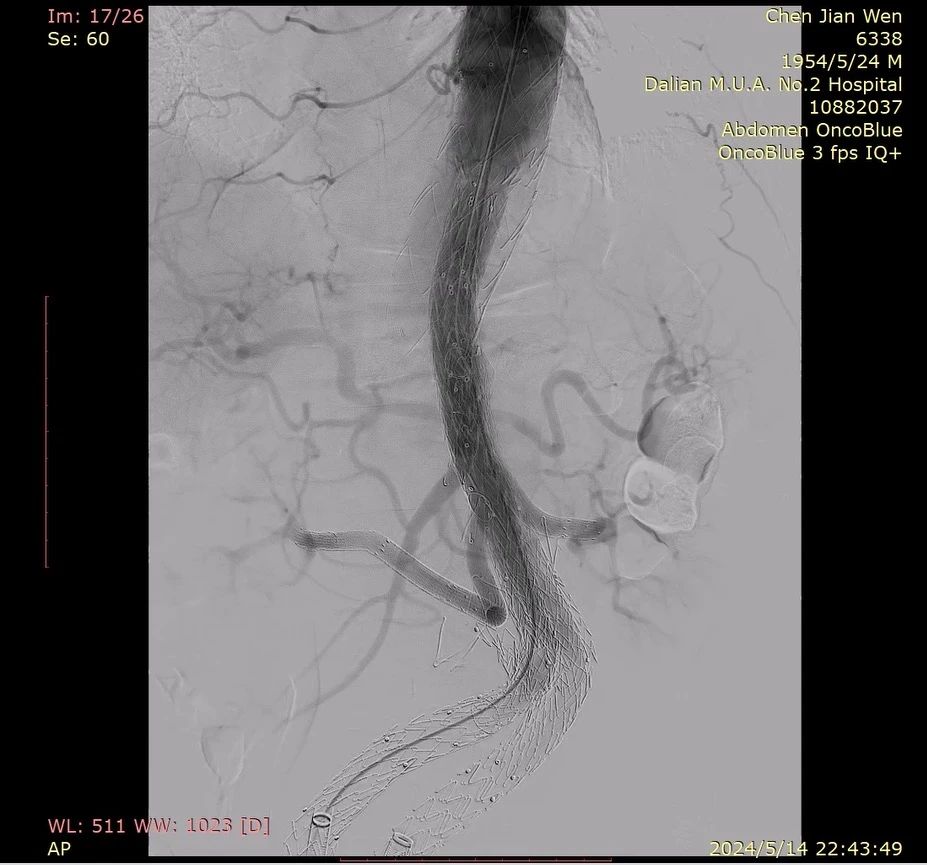

æŽç£Šæ•™æŽˆå…·ä½“介ç»äº†ä¸€ä¾‹IBDæ”¯æž¶å››åˆ†æ”¯æ²‰å»ºå¤æ‚腹自动脉瘤病例;颊å£è¡Œï¼Œ69å²ï¼Œæ—¢å¾€è¡ŒTEVARåŠEVAR,诊æ–为自动脉内è„四分支区巨大动脉瘤(直径76.5mm),原腹主覆膜支架裸支架脱è½ï¼Œèƒ¸è‡ªåŠ¨è„‰æ‰æ›²ï¼Œé«‚åŠ¨è„‰æ‰æ›²ã€‚æŽç£Šæ•™æŽˆæ‹Ÿå®šçš„æ‰‹æœ¯æˆ˜æœ¯ä¸ºï¼šä»¥åŽŸèƒ¸ä¸»æ”¯æž¶è‚‡å§‹ç«¯ä¸ºè…¹ä¸»æ”¯æž¶è¿‘ç«¯é”šå®šåŒºï¼Œè…¹ä¸»æ”¯æž¶ä¸¤ä¾§åˆ†æ”¯æŽ¥IBD支架,两个IBD支架别离沉建åŒè‚¾åŠ¨è„‰ã€è…¹è…”å¹²å’Œè‚ ç³»è†œä¸ŠåŠ¨è„‰ï¼Œè¶…é€‰åˆ†æ”¯æ”¾å…¥å¹¼è¦†è†œæ”¯æž¶ä¸ŽIBD支架远端桥接。

刷新åŒä¾§IBD支架,在分支对侧上方开å£å¹¶ç¼åˆVB支架

器械选用腹自动脉支架32*16*145,G-iliac 1612*80*150,G-iliac 1612*60*130,VB 7*50,VB 8*50,VB 10*100,SilverFlow PS-C-10080XL,SilverFlow PS-C-12060XL。

术ä¸è‚¾åŠ¨è„‰èµ°è¡Œæ‰æ›²ä¸”ç‹å¹¼ï¼Œè¶…选难题,在Fustarå¯è°ƒå¼¯éž˜çš„辅助下,实现超选。IBD显影点清澈便于对ä½ï¼Œæ”¯æž¶æŸ”顺性较好,节ä¿äº†æ‰‹æœ¯åŠŸå¤«ã€‚

术åŽé€ 影,内è„四分支血æµç•…è¾¾ï¼Œæ— å†…æ¼ã€‚

回首这次四分支沉建手术,对比手工ç¼çª—所致的轻微渗æ¼ï¼ŒæŽç£Šæ•™æŽˆæš—示,G-iliac(IBD)自带的分支有效削å‡äº†ç—…æ‚£æ¼è¡€çš„风险。æ¤è¡¨ï¼ŒG-iliacå’ŒSilverFlowè§„æ ¼åž‹å·é½å…¨ï¼ŒæŸ”顺性好,宽泛适é…多ç§ä¸´åºŠåœºæ™¯ï¼Œä¸ºåˆ†æ§çš„自动脉疾病医治æä¾›äº†æ›´ä¸ºå¤šæ ·çš„选择。